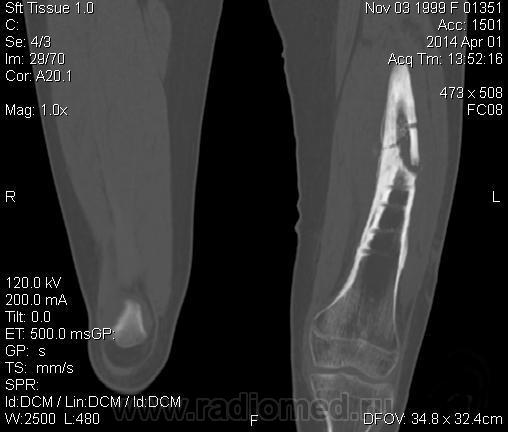

Молодая дама (14 лет) с переломом срдней трети диафиза левого бедра в анамнезе (декабрь 2012 г). Ломала ногу несколько раз в этом месте. Сейчас состояние после МОС. Как следует понимать изменения в кости, формируется ли ложный сустав?

Похоже ложный сустав сформировался. Но при нём обычно большие напластования костной мозоли, здесь их нет. В таких случаях смотрю при скопии подвижность.

Ох, не хочется думать о ложном суставе в 14 лет... По срокам под ложный сустав подходит, он характеризуется замыканием костномозгового канала с формированием подобий суставных поверхностей. У нее же есть хиленькая периостальная костная мозоль по задней поверхности бедра удерживающая отломки в правильном положении. Я склонна думать, что это скорее застарелый перелом (оно же замедленная консолидация). Здесь очень важно посмотреть предыдущие снимки (поиск рефрактуры, либо отсутствия полной консолидации).

Настоящего, родного ложного сустава пока нет, хотя костномозговой канал дистального отломка уже закрыт - образовалась склерозированная замыкательная пластина. Варусная деформация почти в 165 градусов... Я бы заключилась неполной консолидацией и варусной деформацией, прогностически формирование ложного сустава очень вероятно.